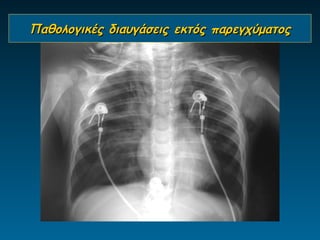

Παθολογικές διαυγάσεις παρεγχύματος

Παθολογικές διαυγάσεις εκτός παρεγχύματος